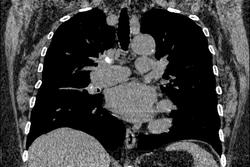

Женщина 72 года. Лечила пневмонию, сделала КТ. Ваши мнения, пожалуйста.

Ну м.б. и был тут туберкулез когда-то. М.б. я не прав, но плотность параплеврального уплотнения к "мясу"(40-50)

т.е. не жидкость. Прослеживаются на этом фоне бронхи. Т.е. ближе к фиброзу легочной ткани, чем к плевриту. Думаю поствоспалительный ( этиологию не спрашивайте) фиброз ( ну, иногда, как перисциссурит пишут, я не согласен с этим), узлы - с кальцинозом, обращаю внимание на центральное четкое кальцинирование, т.е. не острое и не онко.

Фиброз и точка.